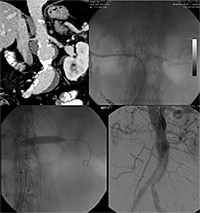

Η πρώτη περίπτωση που αντιμετωπίστηκε αφορούσε παρανεφρικό ανεύρυσμα με συγκεκαλυμμένη ρήξη στο ύψος της μίας νεφρικής αρτηρίας (εικ.1). Η δεύτερη περίπτωση αφορούσε παρανεφρικό ανεύρυσμα, το οποίο παρουσιάστηκε σε ασθενή που είχε ήδη αντιμετωπιστεί ενδαγγειακά προ 4ετίας σε άλλο νοσοκομείο.

Μέσα από τις οπές και τους κλάδους αυτούς καθετηριάζονται τα νεφρικά και σπλαχνικά αγγεία (εικ.2,3), τα οποία διασφαλίζονται και επαναιματώνονται με νέα μικρότερα ενδαγγειακά μοσχεύματα που εισάγονται μέσα από το κύριο μόσχευμα.

Με τον τρόπο αυτό το ανεύρυσμα αντιμετωπίζεται εξ’ολοκλήρου ενδαγγειακά (εικ.4) υπό ακτινοσκοπικό έλεγχο μέσω 2 μικρών τομών στις βουβωνικές χώρες και με σημαντικά μικρότερα ποσοστά νοσηρότητας και θνητότητας.

Εικόνα 1. Παρανεφρικό ανεύρυσμα κοιλιακής αορτής (οι δύο νεφρικές αρτηρίες εκφύονται ακριβώς στο όριο του ανευρυσματικού σάκου).

Εικόνα 2,3. Καθετηριασμός των νεφρικών αρτηριών μέσω των θυρίδων του μοσχεύματος και τοποθέτηση των νεφρικών stents.

Εικόνα 4. Τελική αγγειογραφική εικόνα μετά την τοποθέτηση των νεφρικών stents και τον πλήρη αποκλεισμό του ανευρύσματος.